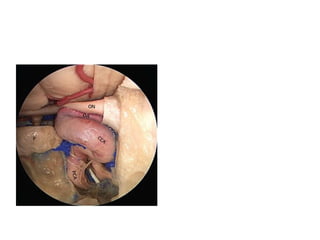

A segment of the orbital portion of the optic

nerve has been removed. This exposes the

branch of the inferior division of the

oculomotor nerve, which passes below the

on optic nerve, pr proximal ring, cdr carotid dural

ring= upper dural ring , ica internal carotid artery